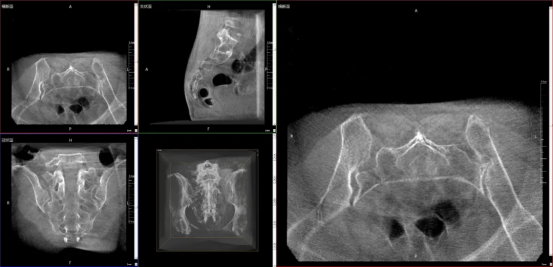

3. 3D C-arm

01 Fluoroscopic Vision: Intraoperative 3D Imaging

The device provides full-field 3D images during surgery, helping doctors to assess screw implantation angles and fracture reduction accuracy in real time. It acts like a "fluoroscopic vision" for surgeons, making intraoperative procedures more precise and efficient.

02 Full Field of View: Large Flat Panel for One-Time Imaging

The device’s large field-of-view flat-panel detector can cover the entire lumbar spine, bilateral sacroiliac joints, and unilateral pelvis in a single exposure. This eliminates the need for repeated adjustments by the technician due to incomplete views, thereby improving operational efficiency and reducing radiation risks from multiple exposures.